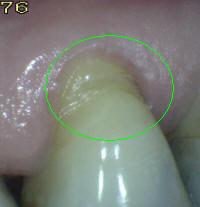

Código 0:

La

superficie de la raíz

no presenta ninguna

coloración

inusual

que lo distingue de

los alrededores o

las áreas adyacentes

de la raíz,

ni

exhibir un

defecto de la superficie,

ya sea en

la unión cemento-esmalte

o totalmente en

superficie de la raíz.

tiene un contorno

anatómico

natural. Ver imagen inferior.